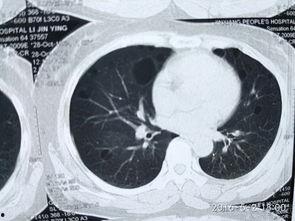

肺上界叩诊的主要目的是检查肺部是否有异常,如肺炎、肺结核等。